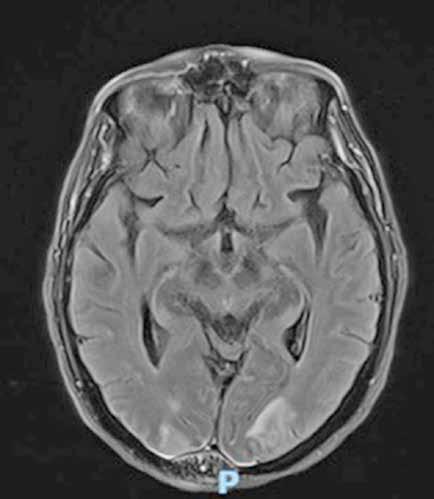

Es ingresado en Medicina Interna en mayo de 2022 por cuadro de fiebre de origen no filiado acompañado de astenia crónica y artralgias múltiples (especialmente en hombro izquierdo). Se administra ceftriaxona intravenosa con buena evolución del proceso febril. No se aísla ningún microrganismo en estudio microbiológico. En el análisis sanguíneo al ingreso destacan los siguientes valores: Hemoglobina 9,1 g/dL; Volumen Corpuscular Medio 105,5 u^3; Leucocitos 8200/L; Neutrófilos 6900/L; Plaquetas 64000/L. En la morfología de sangre periférica se observaban hematíes en lágrimas. Se realiza tomografía computarizada toracoabdominal en el que destaca esplenomegalia de 14 cm, quiste hidatídico hepático y múltiples nódulos milimétricos en ambos lóbulos pulmonares inferiores (Figura 1).

Se realiza medulograma, con el diagnóstico de síndrome mielodisplásico con displasia unilínea (megacariocítica) e hipoplasia eritroide. Asimismo, destaca vacuolización en precursores mieloides y eritroide (Figura 2), motivo por el que se solicita estudio molecular en médula ósea dirigido a estudio de mutaciones en el gen UBA1.

En el estudio citogenético en médula ósea mostró un cariotipo normal. Mientras, el estudio molecular mostró la presencia de alteración para el gen UBA1 detectándose la mutación c.122T>C (p.Met41Thr) en el gen UBA1. El gen JAK2V617F no está mutado.

Dados estos hallazgos se diagnostica al paciente de síndrome de VEXAS asociado a síndrome mielodisplásico unilínea (megacariocítica) de riesgo IPPS bajo e IPSS-R bajo. Tras el diagnostico se inicia tratamiento con tocilizumab intravenoso mensual y eritropoyetina semanal.